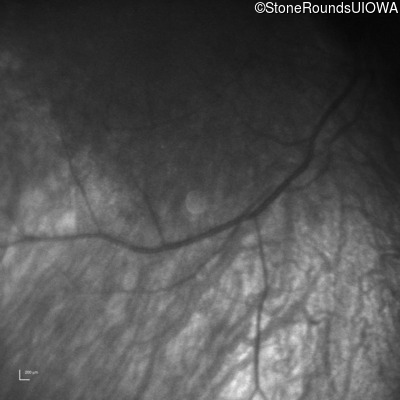

Infrared Fundus Photograph - Right -

No Light Perception

Exemplar

Expanded OCT Stack

×